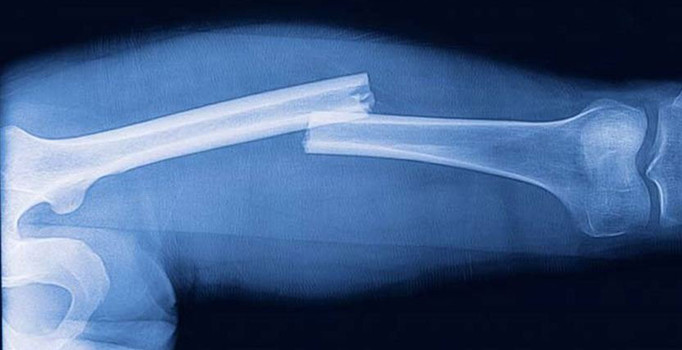

Projeyle ilgili olarak Anadolu Üniversitesi Mühendislik Fakültesi Malzeme Bilimi ve Mühendisliği Bölümü öğretim üyesi Prof. Dr. Nuran Ay, projeyle ilgili şu bilgileri verdi: “Normalde kemiklerin iyileşmesi çok uzun zaman alıyor ve pek çok enfeksiyon meydana gelebiliyor. Bu yeni geliştirilen malzemeyle kemik iyileşmesi normal süresinin yarısı kadar bir zamanda gerçekleşiyor. Enfeksiyon riski yok, beklenen süresinin yarısı kadar süreçte kemik iyileşmesi meydana geliyor. Bu buluş, kırık problemi yaşayan kişilerin yaşam kalitesini yükseltecek.”

Prof. Dr. Nuran Ay, projeyle kemik kırıklarının iyileşmesi ve kemik hasarlarının giderilmesi amacıyla yeni implant malzemeler tasarladıklarını söyledi.